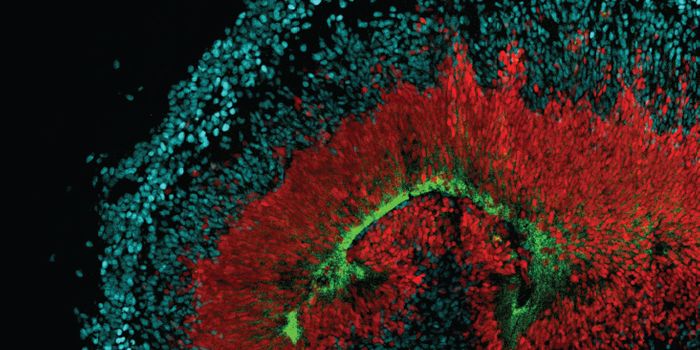

MAR 30, 2016Health & MedicineResearchers claim to have pinpointed the neural stem cells that Zika seems to be targeting. The Zika virus outbrea ...